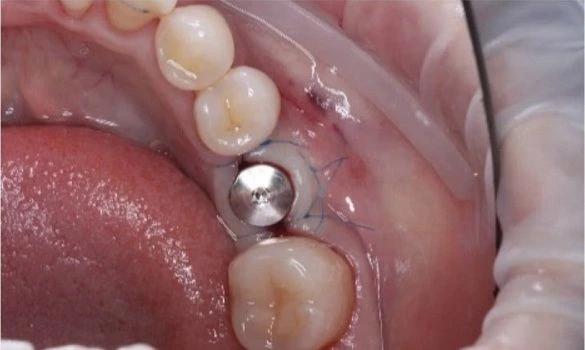

Такие микропротезы можно ставить на жевательные зубы. Часто их используют для установки на импланты.

- имплантация;

- С помощью коронок Е-мах можно как скрыть потемнения и сколы на эмали, так и полностью восстановить сильно разрушенный или отсутствующий зуб.

Основные этапы установки Е-max: